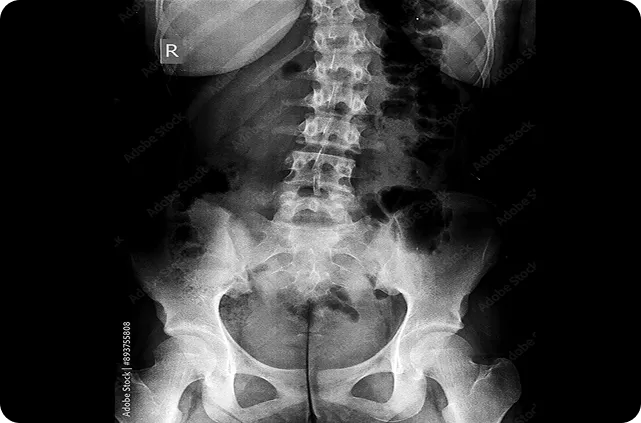

La espondiloartritis axial es una enfermedad inflamatoria crónica del esqueleto axial que termina en nueva formación ósea predominantemente en la columna vertebral y las articulaciones sacroilíacas, llevando a daño estructural progresivo e irreversible, con posterior discapacidad y deterioro de la funcionalidad y la calidad de vida. Se ha reportado que del 10 al 40% de los pacientes con la forma no radiográfica de la espondiloartritis axial progresan a la forma radiográfica en 2-10 años desde el inicio de síntomas. Por lo anterior, la detección y el manejo temprano de la nr-axSpA es esencial para la prevención del daño estructural irreversible, y la progresión a la variante radiográfica. El presente estudio presenta un análisis exploratorio de los cambios radiográficos y la inflamación espinal en pacientes con nr-axSpA activa en manejo con secukinumab durante un período de dos años, proporcionando uno de los conjuntos de datos de imágenes más grandes en pacientes con nr-axSpA disponibles hasta la fecha.

La progresión radiográfica se evaluó usando radiografías convencionales, y el curso de inflamación se evaluó con resonancia magnética de la articulación sacroilíaca y la columna vertebral en el curso de los dos años. Se obtuvieron las radiografías al iniciar el estudio y en la semana 104, las imágenes por resonancia de la columna y las articulaciones sacroilíacas al iniciar el estudio y a las semanas 16, 52, y 104; y se clasificaron utilizando el modified New York scoring system (mNY) para radiografía de la articulación sacroilíaca, el Stoke AS Spine Score (mSASSS) para radiografía de la columna vertebral, el Berlin modification of the AS spine MRI (ASspiMRI) para resonancia magnética de la columna vertebral, y el Berlin Active Inflammatory Lesions Scoring (BAILS) para edema de médula ósea en resonancia magnética de la articulación sacroilíaca. El objetivo del artículo es proporcionar información sobre el efecto en progresión radiográfica e inflamación del tratamiento con secukinumab en pacientes con nr-axSpA.

Un total de 438/555 (78.9%) de los pacientes completaron las 104 semanas del estudio. En general, 50.8% de los pacientes en el grupo de secukinumab con dosis de carga, 47.3% en el grupo de secukinumab sin dosis de carga, y 64% de los pacientes del grupo placebo cambiaron a secukinumab o estándar de tratamiento (sólo 3 pacientes cambiaron a estándar de tratamiento). El estudio encontró que la media de los puntajes basales de sacroileítis (en un rango de 0-8 en el mNY) fue de 1.45 (SD=1.53) en el grupo de secukinumab y de 1.47 (SD=1.60) en el grupo placebo-secukinumab; en la semana 104 los puntajes fueron de 1.41 (SD=1.47) y 1.50 (SD=1.61), en el grupo de secukinumab y secukinumab-placebo respectivamente. En general, 87.7% de los pacientes en el grupo de secukinumab y 85.6% de los pacientes en el grupo placebo-secukinumab mostraron no-progresión en el puntaje mNY para la articulación sacroilíaca a la semana 104 (no-progresión se definió como un aumento en el puntaje de sacroileítis menor o igual al cambio detectable más pequeño, que se situó en 0.46 en un límite de concordancia del 80%).

En cuanto a las radiografías de la columna vertebral, los puntajes basales del mSaSSS fueron de 0.68 (SD=2.35) en el grupo secukinumab y de 0.81 (SD=2.37) en el grupo secukinumab-placebo; a la semana 104, los puntajes fueron de 0.73 (SD=2.49) en el grupo secukinumab, y de 0.88 (SD=2.60) en el grupo secukinumab placebo. En general, 97.5% de los pacientes en el grupo secukinumab, y 97.1% de los pacientes en el grupo secukinumab-placebo mostraron no-progresión estructural a lo largo de los dos años (definida como un cambio en el puntaje mSaSSS menor al cambio detectable más pequeño, que se situó en 0.76 en un límite de concordancia del 80%).